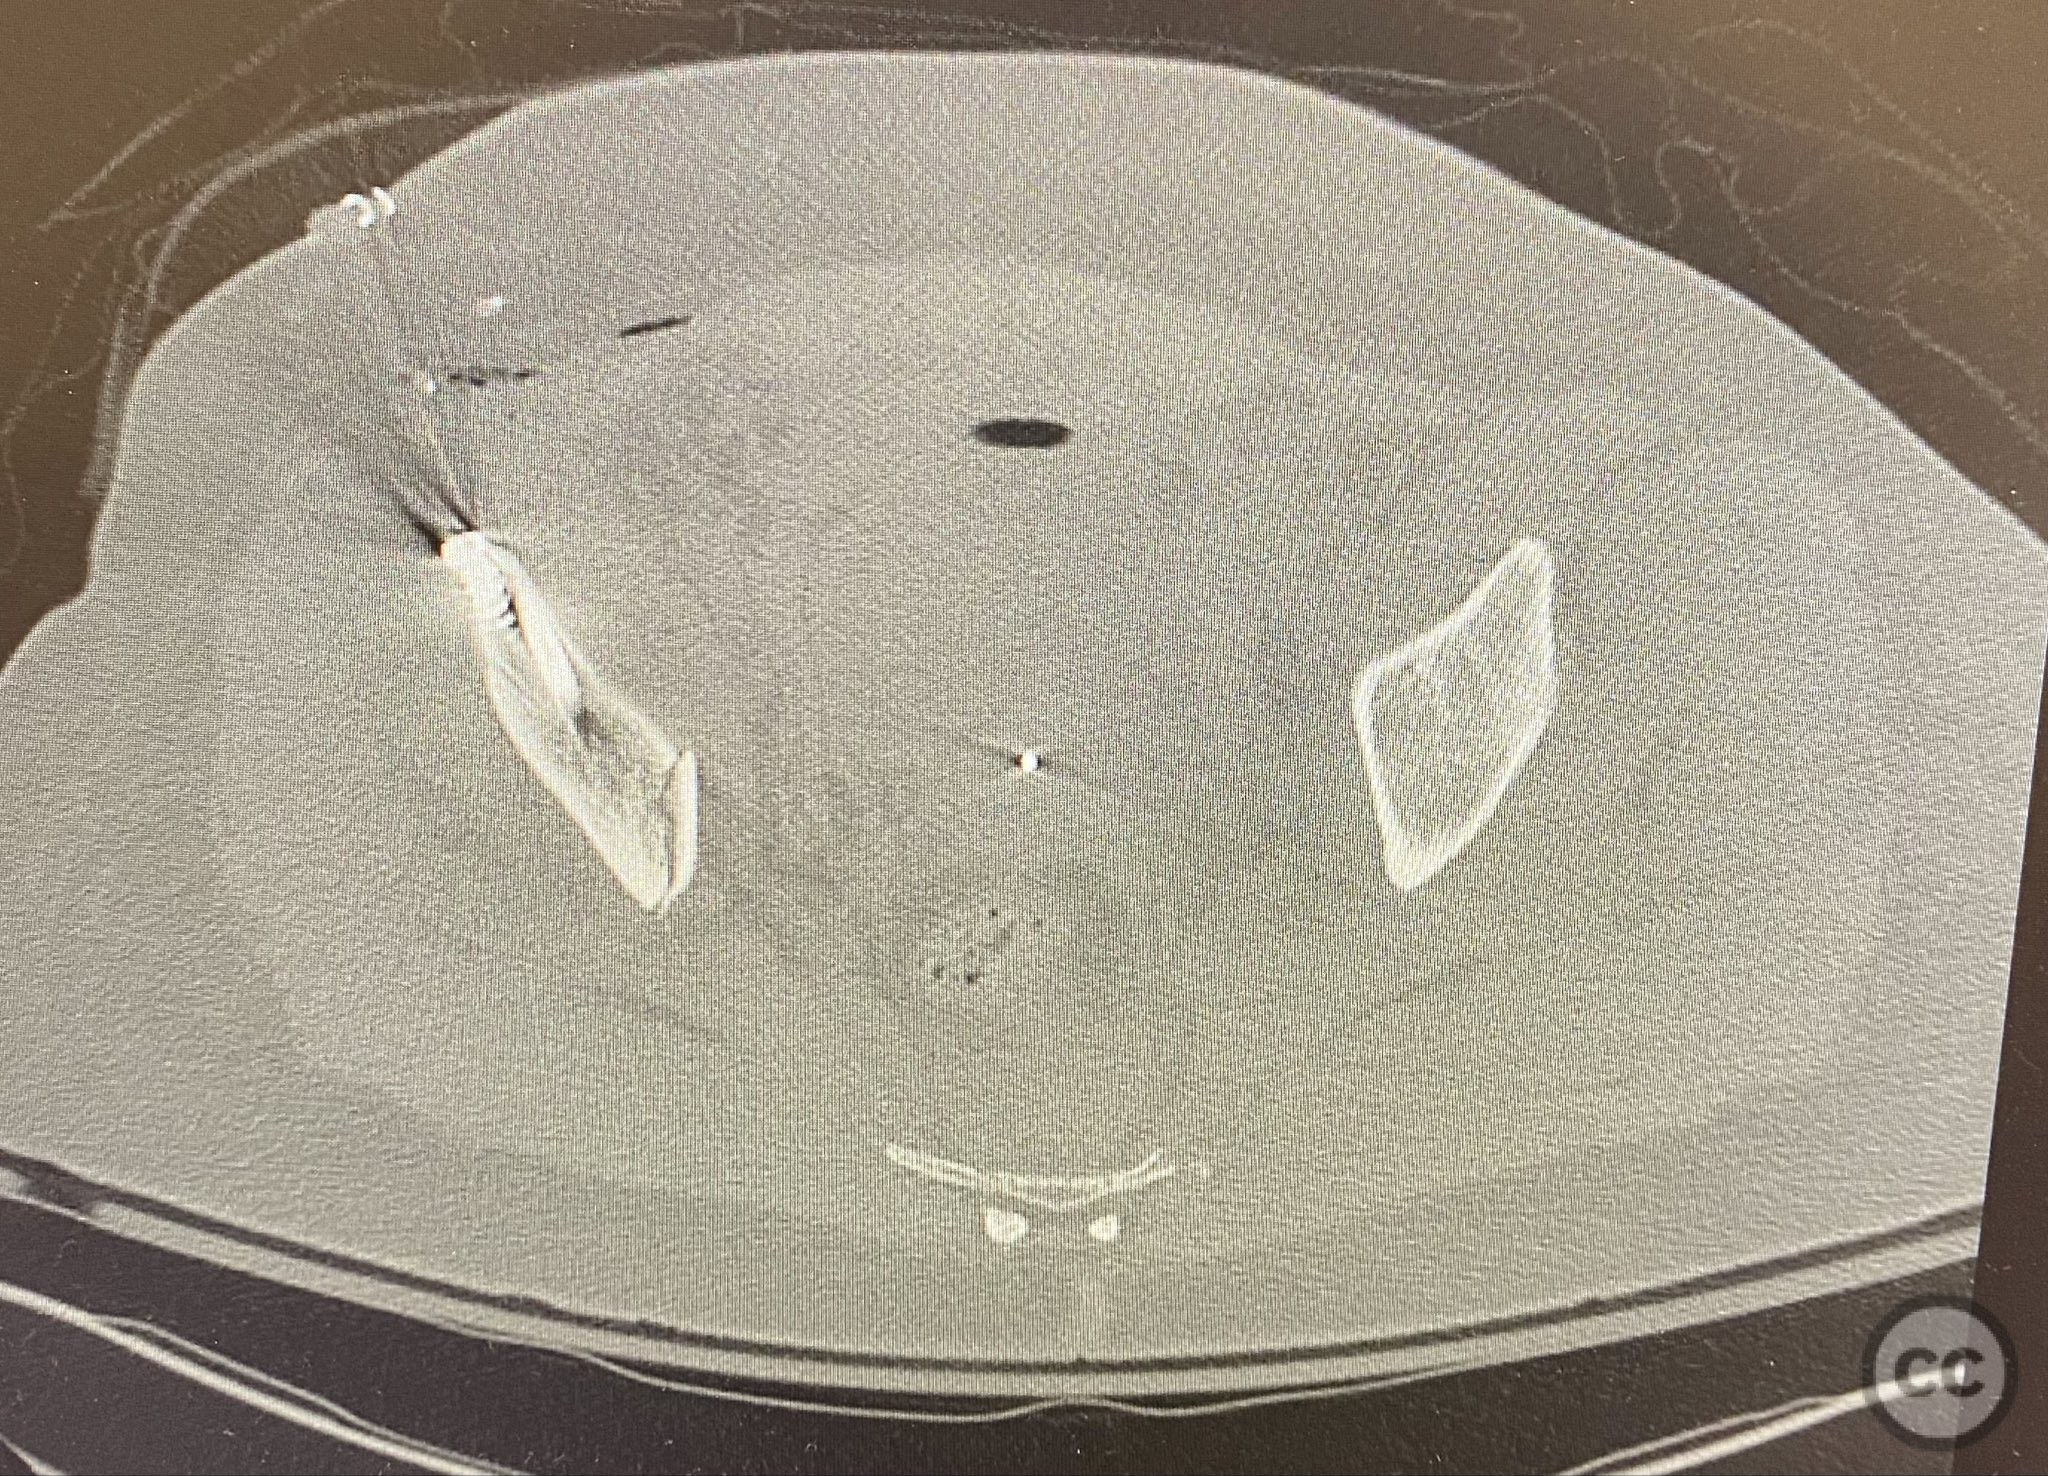

Clinical Details

Clinical and radiological findings:  The patient presented following trauma with an unusual, significantly displaced right iliac fracture, accompanied by left-sided sacral and parasymphyseal ramus fractures. Initial AP pelvic radiography demonstrated the complex injury pattern. CT imaging provided detailed characterization of the iliac and sacral fractures, including assessment of displacement, bone quality, soft tissue status, and overall body habitus. No neurovascular compromise was reported. AO/OTA classification: Right iliac fracture 61B2.3 (partial unstable, lateral compression injury), left sacral fracture Denis zone I, left parasymphyseal ramus fracture.

Anatomical surgical approach:  A standard anterior ilioinguinal approach was utilized for the right iliac fracture. Dissection proceeded through the skin and subcutis, with identification and protection of the lateral femoral cutaneous nerve. The external oblique aponeurosis was incised, and the iliacus muscle was elevated subperiosteally from the internal iliac fossa to expose the fracture site. Reduction was achieved under direct visualization, followed by internal fixation with a contoured plate and pelvic brim cancellous screws, ensuring all implants were contained within the osseous fixation pathway. The left sacral fracture was stabilized percutaneously under fluoroscopic guidance.

Bilateral distal femoral traction resulted in excellent reduction of the sacral fracture but did not adequately reduce the iliac displacement. Percutaneous fixation of the sacrum was performed first, followed by open reduction of the iliac fracture. Intraoperative imaging confirmed that all implants were fully contained within the available osseous corridors, avoiding extraosseous penetration. The complexity of the iliac fracture required careful anatomical reduction and implant placement along the pelvic brim.